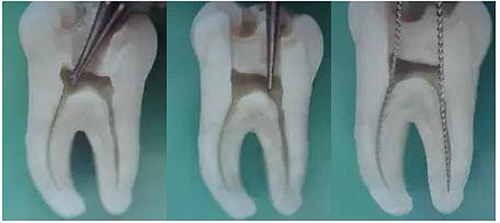

3、根管口的直線通道:特別對(duì)于彎曲根管!預(yù)備根管之前是否重視這個(gè)環(huán)節(jié),盡管找到了根管口,銼也能順利進(jìn)入根管,但根管口的直線通道是否建立也是衡量醫(yī)生操作技能的重要依據(jù)。

方法很多:手動(dòng)器械操作時(shí)我們可以采用價(jià)格便宜的“GG”鉆,PROTAPER機(jī)動(dòng)預(yù)備時(shí)可以采用SX銼。

圖7彎曲根管冠部處理之前 圖8用GG鉆或SX銼進(jìn)行預(yù)備

圖9處理后形成的直線通道

我的病例1_冠部處理成直線通道后的充填效果

我的病例2_下頜7"C"型根管的充填效果